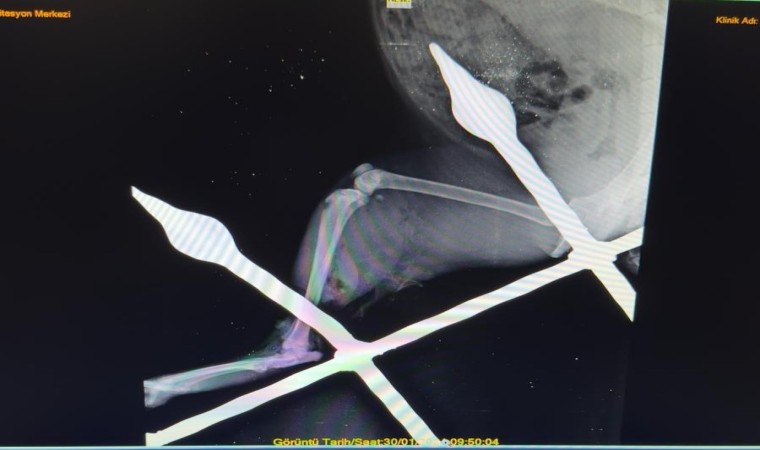

Yaralı kedinin bacağını eski sağlığına kavuşturduklarını anlatan Mersin Büyükşehir Belediyesi Tarımsal Hizmetler Dairesinde Veteriner Hekim olarak görev yapan Yusuf İncir, “Yapılan ilk tespitler sonucunda, balkon demirinin bacağından yaklaşık 10-15 santimetre civarında geçtiği görülmüştür. Yapılan dezenfeksiyon ve temizlik işlemlerinin ardından, balkon demiri anestezi altındaki kedinin bacağından çıkarıldı. Çıkarılırken dokuya mümkün olduğu kadar zarar vermemeye dikkat ettik. Yaptığımız tespitlerde kaslardan bir tanesinin kopmuş olduğu, yalnız sinir dokusunda herhangi bir hasar oluşmadığı tespit edilmiştir. Yapılan yara temizliği ve dezenfeksiyonun ardından, kopan kas kısmı dikişle tekrar eski haline getirildi. Dezenfeksiyonun ardından, yırtılan ve hasar gören dokuların dikiş işlemini gerçekleştirdikten sonra, deri dikişi ile işlemimizi tamamladık. 12 gün zarfında kedimiz sağlığına kavuştu” ifadelerine yer verdi.